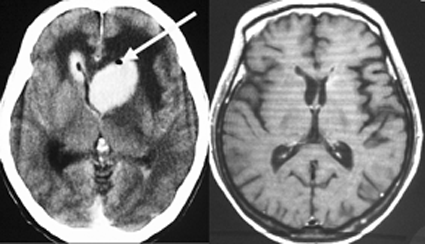

矢印の所を定位脳手術で取りました。病理の結果がリンパ腫と確定されましたから,MTX化学療法をしてから放射線をあてたら,右側のMRIのように腫瘍は消えました。患者さんの症状は良くなって退院したのですがーー。

左から,1回目の再発,2回目の再発,3回目の再発です。再発するたびになんとか治療はできるのですが,違った場所に再発してきてだんだん治療が効かなくなってくることが多いです。このような現象から,脳のリンパ腫は脳に発生するのではなくて,体のどこかに原発巣があるのではないかという考えもあります。もちろん、こんな再発をしないで治ってしまう患者さんも多いです。